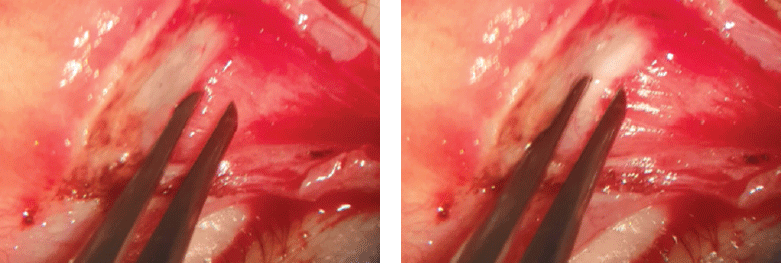

The white line mobility varied significantly from 0 to 4 mm in our cases (Fig. 3, 4).

Fig. 3. Example of 4 mm white line motility

Рис. 3. Пример подвижности белой линии 4 мм